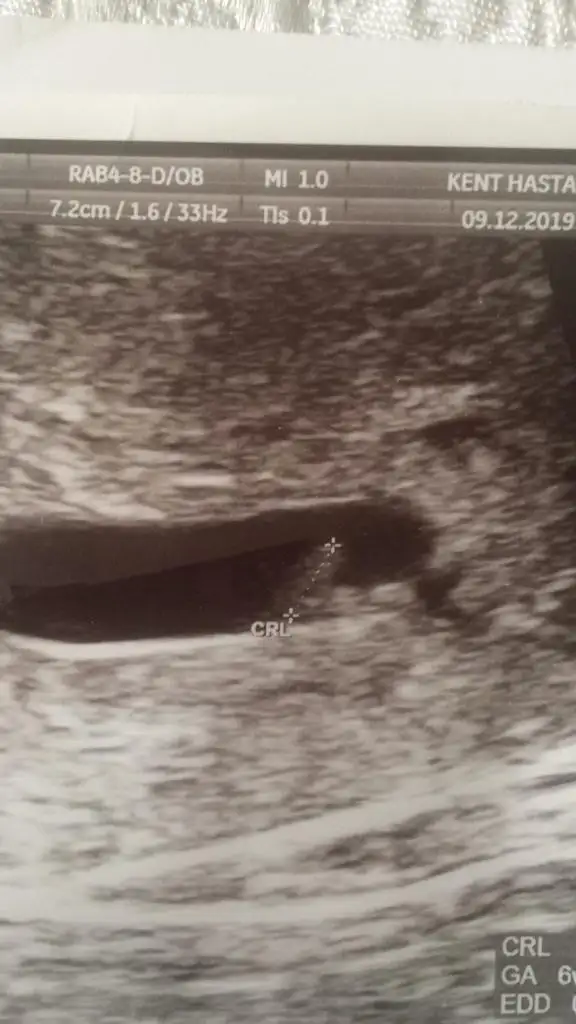

Bebek te mi görünüyor bana mı öyle geldiBu da benim minik davşanım5+0 da göründü tam

kesenin içi doluBu da benim minik davşanım5+0 da göründü tam

senin yolladıgın 6 haftalıkkendı herhalde demı canım

seninkininde içi doluuu5 haftalıktı 10 Aralık’ta 30 Aralık’ta gitcem cok merak ediyorum kalp atışını

evet canımsenin yolladıgın 6 haftalıkkendı herhalde demı canım

6 haftalık ultrason goruntusune benzıyo